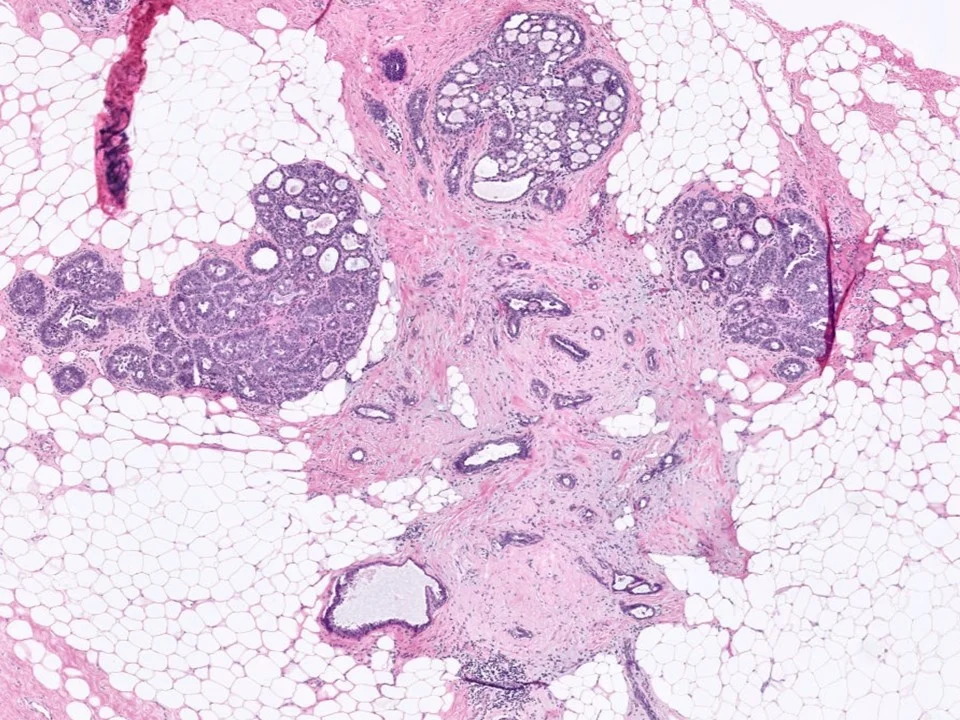

Microglandular Adenosis

Microglandular adenosis is an uncommon proliferative glandular lesion that is important to recognize because it mimics carcinoma clinically and pathologically.

Microglandular adenosis is characterized by an infiltrative, nonlobulocentric proliferation of relatively uniform, small glands within the stroma and adipose tissue.

Microglandular adenosis is composed of small round glands that are lined by a single layer of flat-to-cuboidal epithelial cells. The glands lack an outer myoepithelial cell layer. They often have an eosinophilic, PAS+ Diastase resistant secretory material within the lumina.